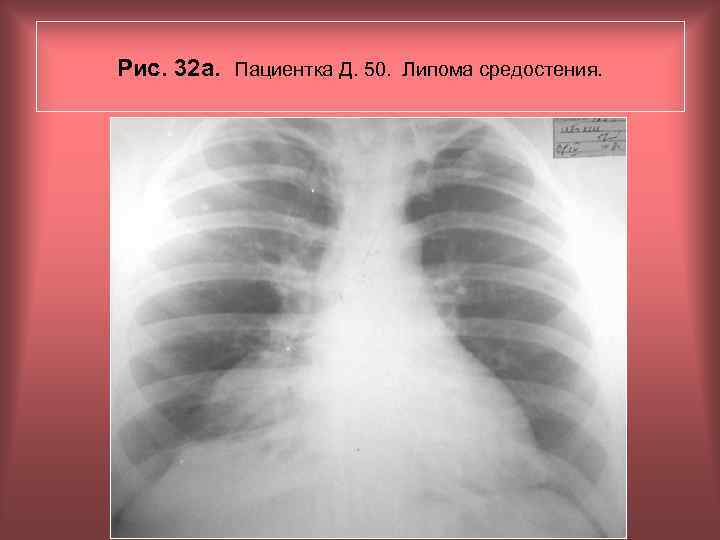

Рис. 32 а. Пациентка Д. 50. Липома средостения. Н. С. Воротынцева, С. С. Гольев Рентгенопульмонология